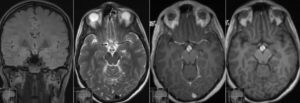

Томография головного мозга, как и гипофиза, помогает обследовать область турецкого седла. В первом случае полученной во время процедуры информации бывает недостаточно, и при постановке диагноза специалист может ошибиться.

МРТ железы гипофиз — это современный неинвазивный способ определения правильности работы органа. В результате обследования получается трехмерное его изображение.

Отличие МРТ головного мозга от томографии гипофиза заключается в следующем: разные объекты обследования, различные показания и технические параметры (проекция, толщина срезов, разрешение изображения). Остальное одинаково.

Для того чтобы правильно расшифровать снимки, следует знать, как выглядит гипофиз без патологий. Для расшифровки используется пять критериев.

- Расположение и форма. Орган расположен в центре турецкого седла и имеет бобовидную форму. Верхний край выпрямлен или немного вогнут. Нижний край повторяет форму турецкого седла. Фронтальная область — прямоугольная, сагиттальная — эллипсоидная. На снимках форма — симметричная.

- Размер. Поперечно составляет 14 миллиметров (совпадает с размером турецкого седла). В переднезадней доле — 11 миллиметров. Высота по средневенечной плоскости — 8 миллиметров. В период беременности норма составляет 12 миллиметров. Вес не должен превышать 1 г.

- Контуры. Четкие, ровные.

- Плотность. Неизменна, гомогенная.